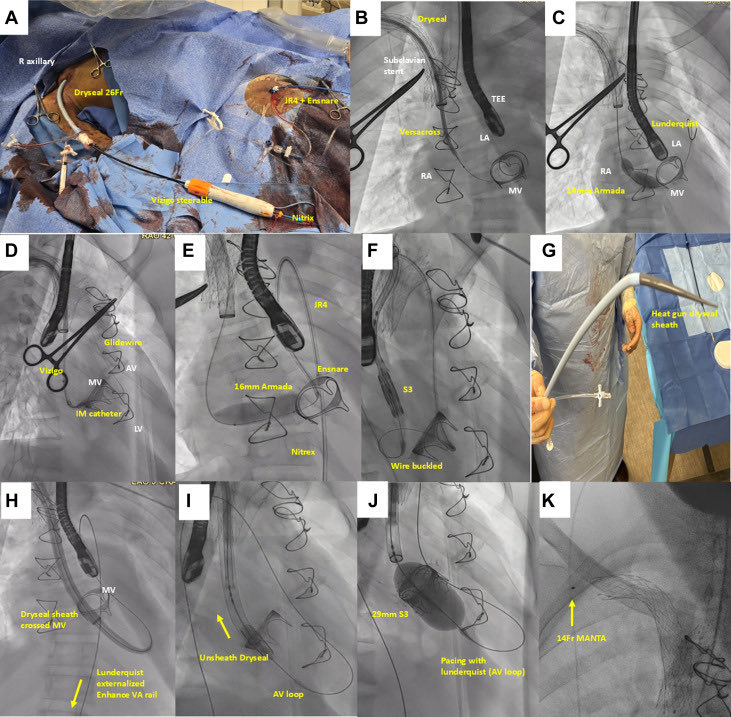

25 days

Just published: Beyond Limits in Alternative Access: The Success of Right Subclavian Transcatheter Mitral Valve Replacement https://t.co/tqabVP6z8e @Brianponeill @PedroMDMSc @engelpedro @GKFram @AhmadJabri8